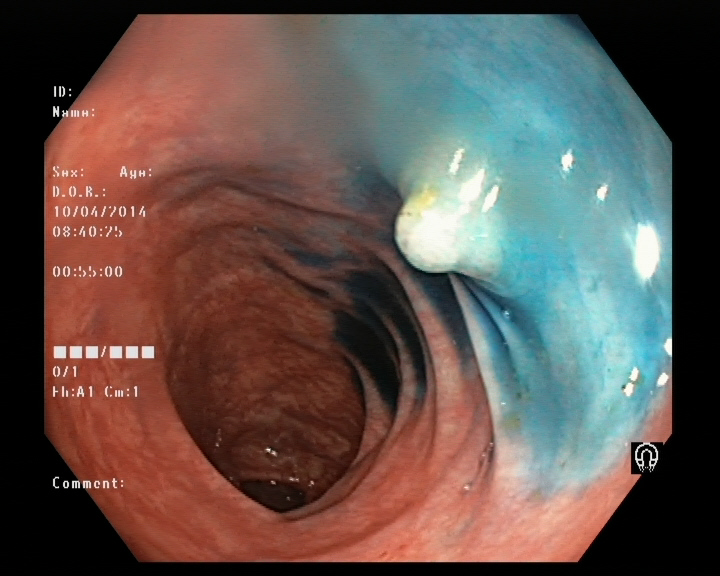

3. KvasirV2 dataset (Pogorelov et al., 2017) is a dataset containing 8000 images from inside the gastrointestinal (GI) tract. The data distribution of this dataset is balanced and can be categorised into 8 classes related to anatomical landmarks and endoscopic polyp removal, listed as ’dyed-lifted-polyps’, ’dyed-resection-margins’, ’esophagitis’, ’normal-cecum’, ’normal-pylorus’, ’normal-z-line’, ’polyps’, and ’ulc-erative-colitis’. Each class consists of 1000 sample images and all of the images have been annotated and sorted by experienced endoscopists.